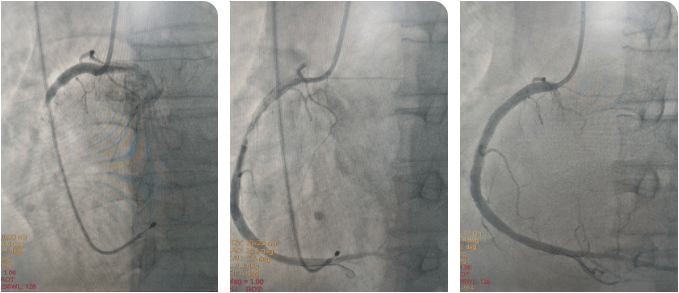

時間就是生命!心內科介入團隊與死神展開較量,大家輪流為患者進行心肺復蘇,并以最快的速度完成消毒、鋪巾。患者大動脈搏動消失,李新國主任、吳利杰主任憑借扎實的基本功,盲穿腋靜脈及右側股動脈,植入臨時起搏器。根據心電圖判斷罪犯血管為右冠狀動脈,李新國主任果斷直接選擇右冠指引導管造影,造影證實判斷,右冠狀動脈粗大,自近段完全閉塞。12:36介入團隊將導絲送到了患者閉塞血管的遠端,并用球囊對閉塞血管擴張后順利恢復前向血流。奇跡出現了,患者微弱的心跳逐漸有力,血壓、心律也逐漸好轉。此時的患者仍處于昏迷狀態,攜帶呼吸機及臨時起搏器轉入CCU病房繼續治療。

術后,在李新國主任、沈靖超主治醫師及段秋燕護士長帶領的護理團隊精心施治、細心護理下,患者于當日意識轉清醒,拔除氣管插管,生命體征穩定,之后也順利渡過心梗后心力衰竭、消化道應激性潰瘍、肺部感染等并發癥,3天后拔除臨時起搏器,1周后于右冠狀動脈動脈植入2枚支架,之后轉入普通病區繼續鞏固治療,并于近期順利出院。